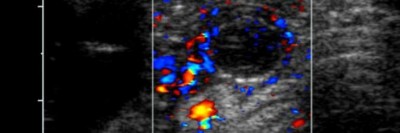

Sehnenschmerz durch Ciprofloxacin: Nach sieben Jahren endlich geheilt

Nach zwei antibiotischen Behandlungen mit einem Fluorchinolon litt ein 69-Jähriger sieben Jahre lang unter extremen Schmerzen in beiden Achillessehnen. Nichts half, bis ein Klinikteam auf die Idee kam, es mit einer speziellen Kombinationsbehandlung zu versuchen.